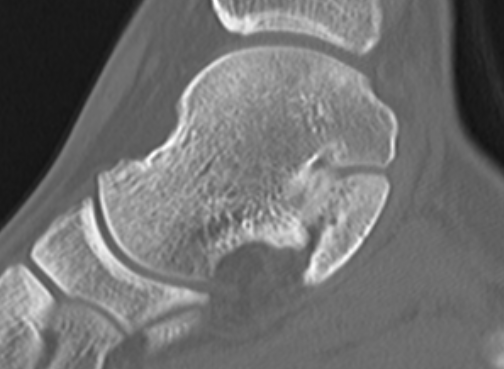

CT

TC coalition middle facet

Complete synostosis of the medial TC joint with OA of the posterior subtalar joint